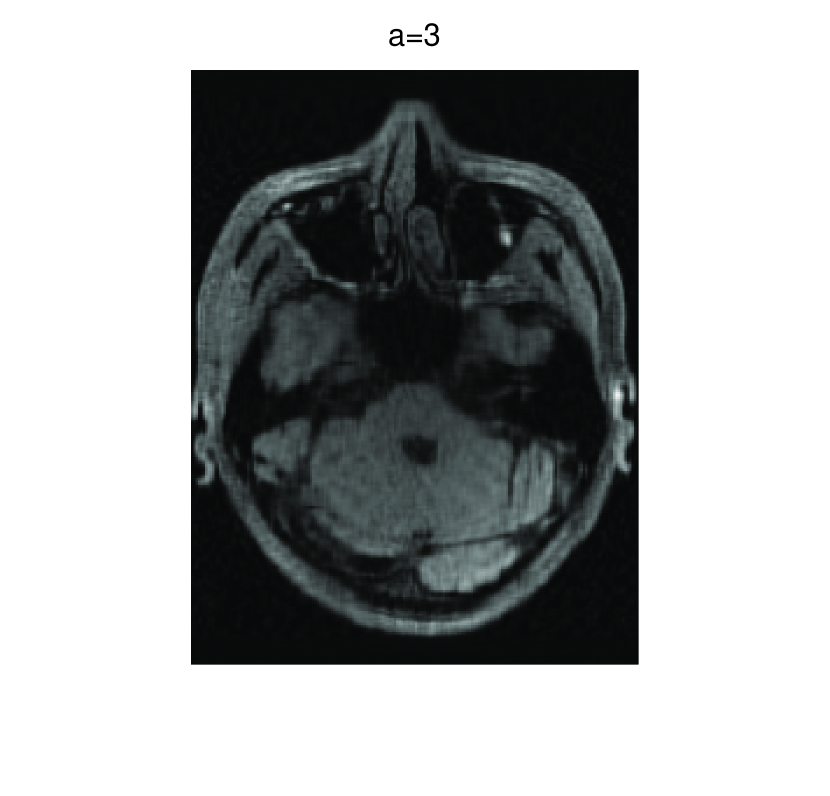

In this subsection, we demonstrate performances of ISVTA on image inpainting problems. The ISVTA is tested on some medical grace images ( Brain angiography image (BAI), Hand angiography image (HAI) and Intracranial venous image (IVI)). We use the SVD to obtain their approximated low-rank images with rank , respectively. Numerical results of ISVTA for theses low-rank image inpainting problems are reported in Table 5, 6, 7, 8.

Table 5, 6 show that ISVTA performs powerful in finding a low-rank matrix on image inpainting problems. Indeed, we could get an exact low-rank image by the ISVTA by choosing proper . Moreover, it is necessary to point out that our method does not work well for all , and we can find that is not a good strategy for the low-rank IVI either or . The numerical results of ISVT, SVTA and SVPA compared in Table 5, 6, 7, 8, 9, 10 under same circumstance show that the ISVT algorithm performs far more better than ISTA and SVPA on image inpainting problems for some proper .